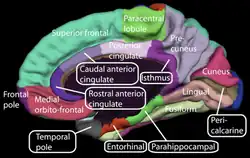

Medial surface of left cerebral hemisphere. (Paracentral lobule is shown in red.) | |

Medial view of a human right cerebral hemisphere. Paracentral lobule is labeled at top center, in green.

Medial view of a human right cerebral hemisphere. Paracentral lobule is labeled at top center, in green. -